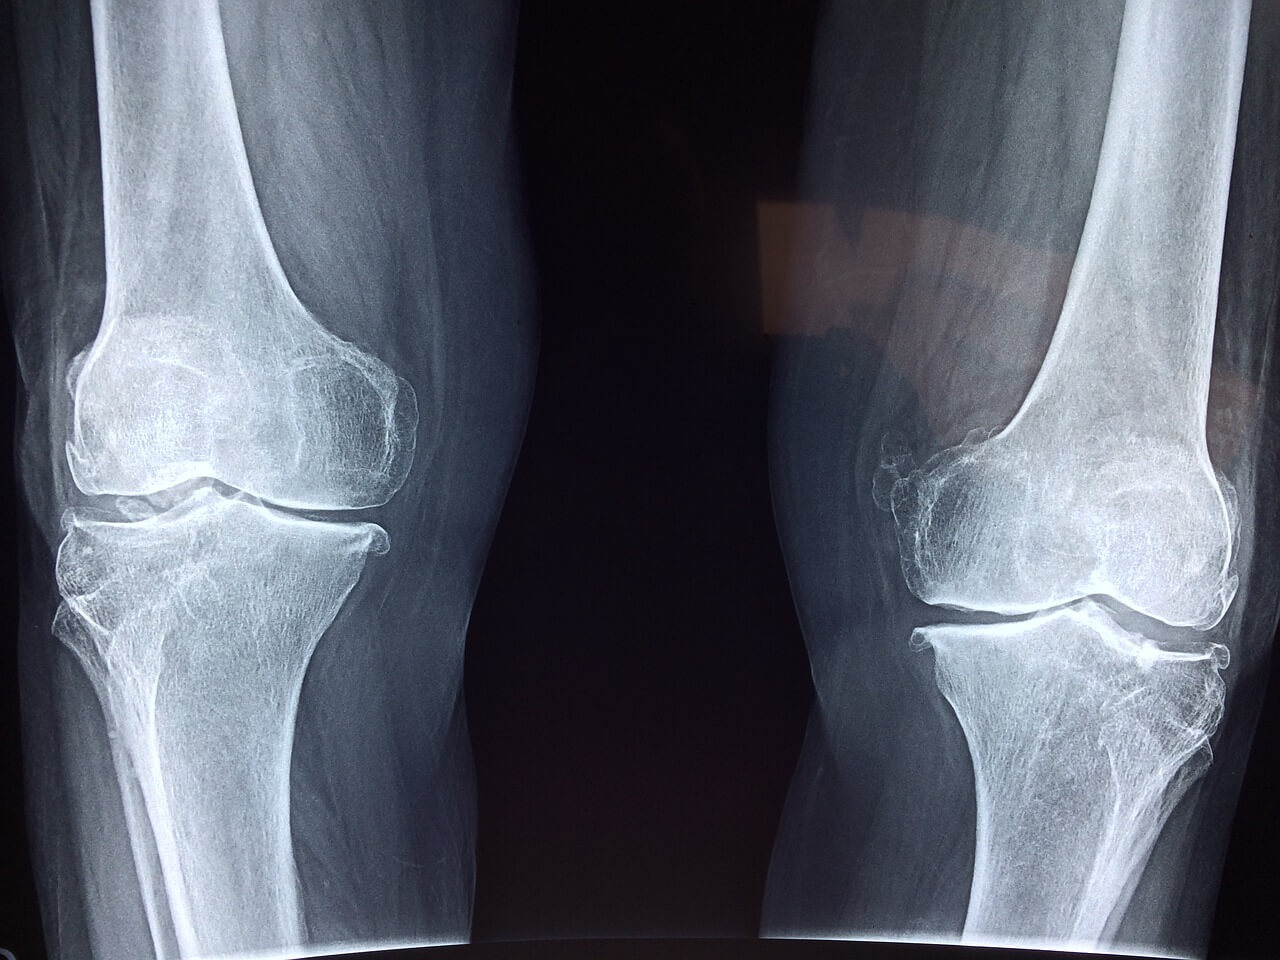

골다공증 검사는 ‘골밀도 검사’라고 불려요. 가장 많이 쓰이는 방법은 DEXA 검사예요.

DEXA 검사는 허리뼈(요추), 엉덩이뼈(대퇴골)를 찍어서 뼈 상태를 확인해요. 누워서 X-ray처럼 찍는 방식이라 통증도 없고 10분 안에 끝나요.